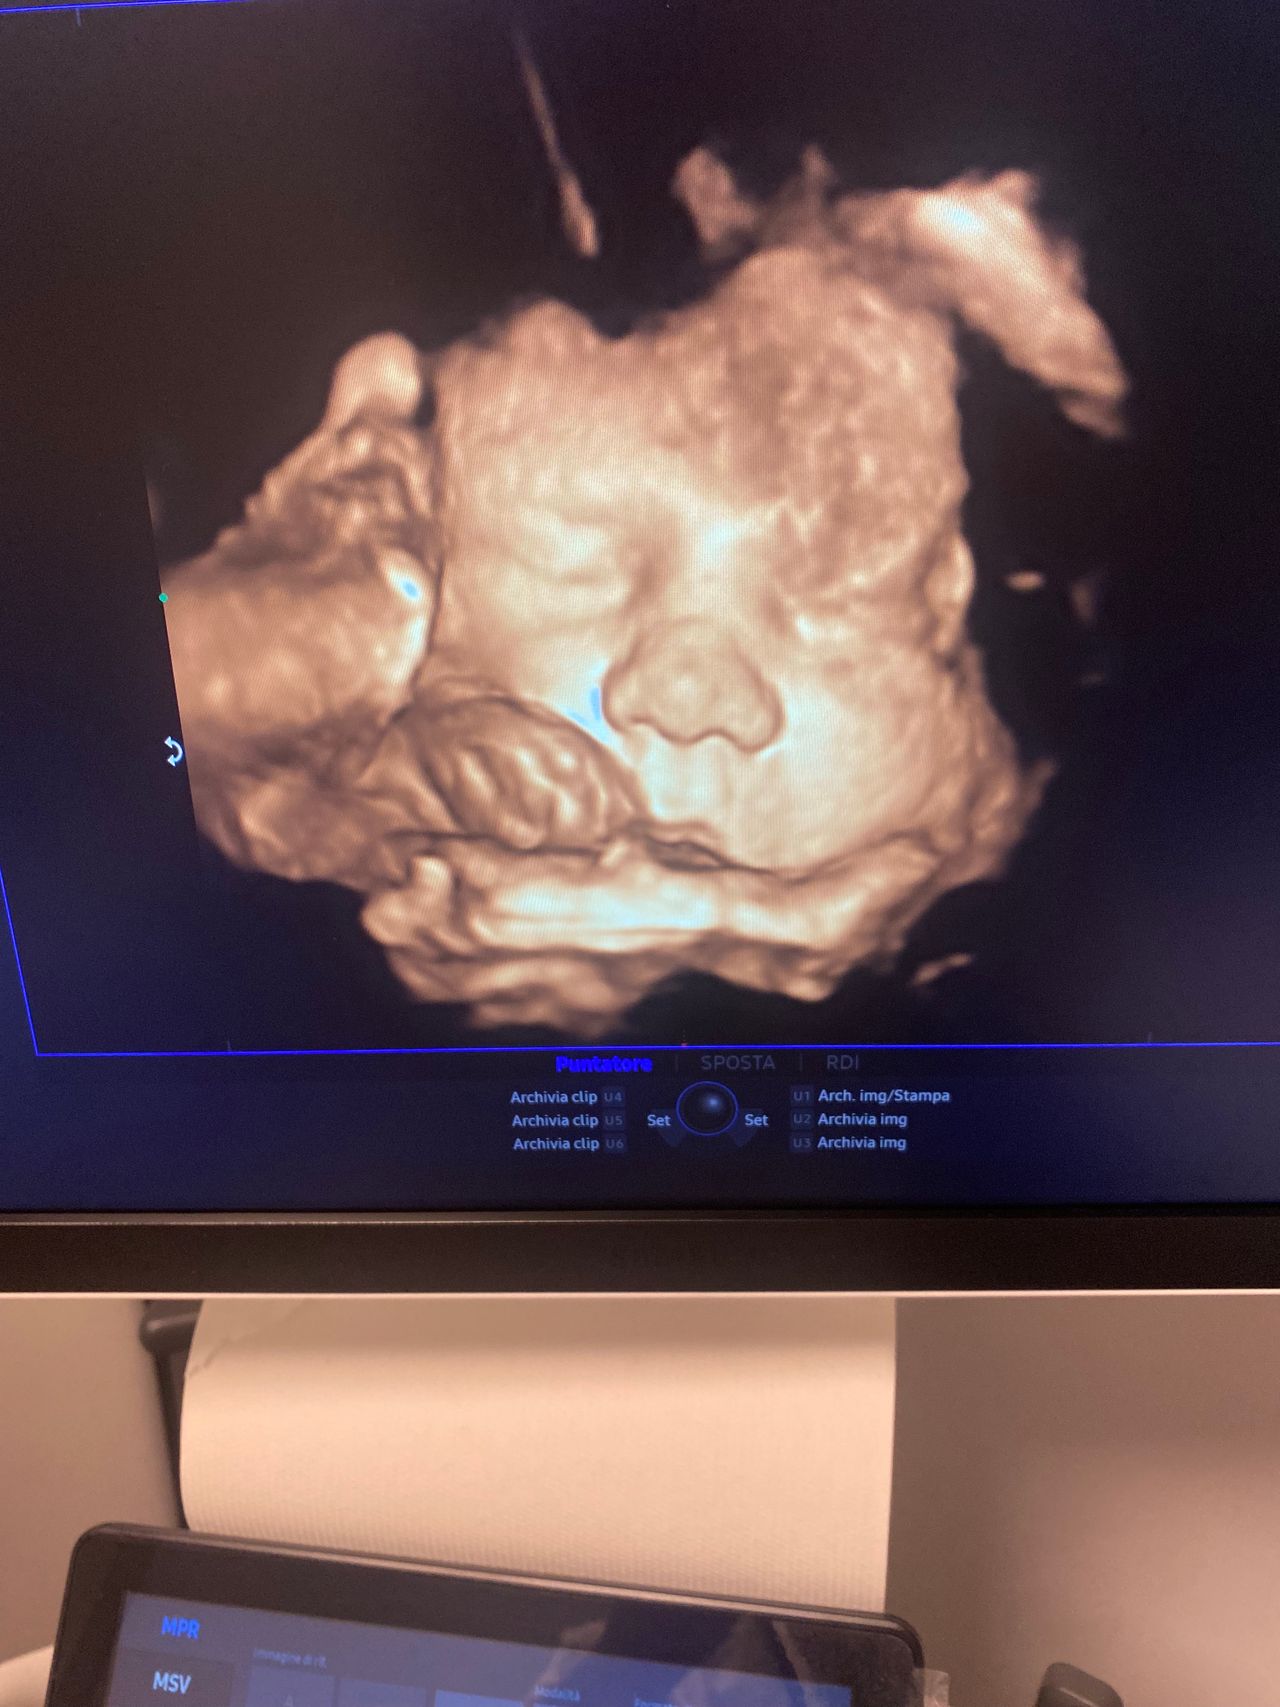

Foto e video